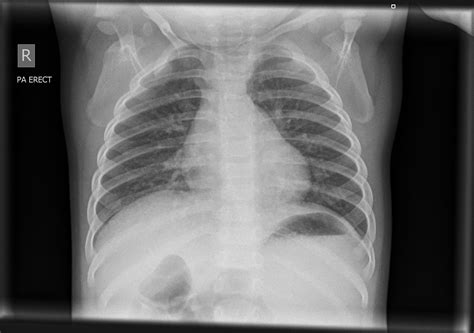

Common Findings in a Normal Chest Ray

A Normal Chest Ray typically reveals the following structures and conditions:

Structure/Condition Description

Lungs Clear lung fields with no signs of infection, inflammation, or tumors.

Heart Normal size and shape, with no signs of enlargement or fluid accumulation.

Ribs and Spine Intact bones with no fractures or abnormalities.

Diaphragm Normal position and movement.

Pleural Space No fluid or air accumulation.